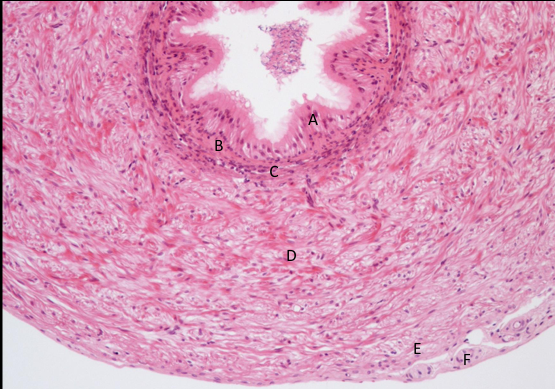

nasieniowód część dystalna nr 416

nabłonek wielorzędowy ze stereociliami

blaszka właściwa

mięśniówka okrężna, podłużna, okrężna

przydanka